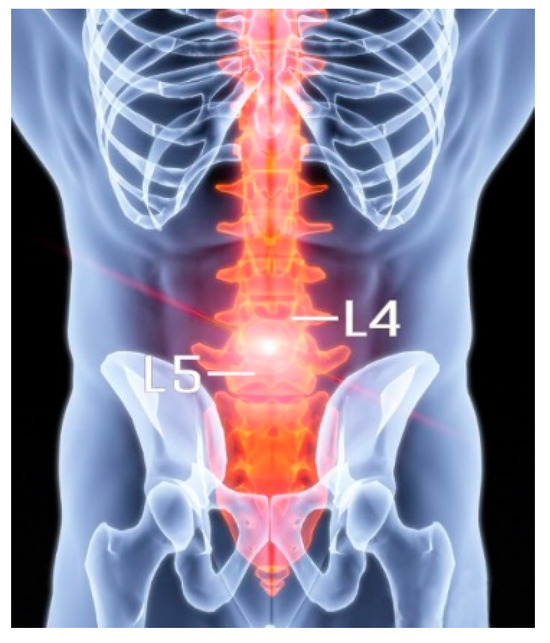

This study presents a novel approach for predicting the location and fatigue life of degenerative intervertebral discs (IVDs) under cyclic loading conditions, aiming to improve the understanding of disc degeneration mechanisms. Based on mechanical theories linking IVD degeneration to stress imbalance and water loss, a finite element (FE) model of the L4–L5 lumbar spine was developed, combining probability-weighted anatomical structures, inverse dynamics, and cumulative fatigue mechanics. By quantifying stress variations and calculating cumulative damage across disc regions, stress-concentration areas prone to degeneration were identified, and validation via a case study of a retired weightlifter diagnosed with intervertebral disc disease (IVDD) demonstrated that the predicted degeneration location correlated well with affected areas observed in CT scan images. These findings suggest that prolonged, abnormal stress imbalances within the disc may contribute significantly to degeneration, offering potential clinical applications in preventive assessment and targeted treatment for spine health.

Accordingly, for this study, we introduced a novel approach for predicting the location and fatigue life of IVDD in the L4–L5 segment. By integrating FEA with inverse dynamics and probability-based statistical methods, we aimed to simulate stress distribution and fatigue behaviour in both normal and degenerated discs. The predictive accuracy of the methodology was evaluated through a case study involving a retired weightlifter diagnosed with IVDD following repeated 125 kg snatch loads. The model demonstrated strong agreement with clinical observations, both in identifying the degeneration location (validated against CT imaging) and quantifying fatigue life. These findings suggest that integrating biomechanical simulations with patient-specific loading profiles could enable pre-emptive identification of at-risk spinal segments, thereby informing targeted prevention strategies for IVDD.

The L4–L5 segmental geometry was reconstructed from high-resolution CT scans of a 24-year-old male weightlifter, height 170 cm and mass 71 kg, who experienced IVD degenerative changes in the L4–L5 segment, as shown in Figure 2, due to long-term high-intensity training.

The predicted results align with the CT imaging data of the retired weightlifter (Figure 2), validating the accuracy of the proposed method. The combined analysis of regional stress distributions (Figure 8) and fatigue life predictions (Figure 10) demonstrated that posterior annulus fibrosus regions (Sections F, H, I) exhibited sustained stress amplitudes exceeding 1.0 MPa—a threshold associated with collagen microfailure—resulting in a 3.2-fold reduction in predicted fatigue life compared to nucleus pulposus regions (Section E, 0.28 ± 0.05 MPa). These findings quantitatively establish stress imbalance as a dominant mechanical driver of localized IVD degeneration.

The model’s predictive accuracy was quantitatively assessed through spatial correlation analysis between predicted high-stress regions and CT-identified degeneration sites in the case study subject. A semi-automated segmentation protocol (ITK-SNAP 4.2.0 software) was employed to map degeneration loci from clinical CT scans to the FE model’s coordinate system, enabling a direct comparison of spatial overlap. The posterolateral annulus regions (Sections H, I) demonstrated concordance between predicted stress concentrations and actual degeneration areas.

Since the annulus fibrosi are thicker on the anterior lateral regions than on the posterior lateral regions, and with the exact location of the nucleus pulposus slightly behind the centre of the IVD, the posterior and posterolateral annulus become weaker mechanically. The anterior part of the IVD mainly bears the compressive stress, while the middle and posterior parts mainly bear tensile stress, and shear force is generated in the IVD. The long-term stress imbalance during weightlifting may have caused the pressure difference in the disc and led to the disc being squeezed from high pressure to low pressure. Hence, the section being squeezed in IVD occurs in the left posterior part of the disc (section A), thus possibly accelerating the degeneration of the IVD under long-term stretching, leading to IVDD. By comparing the CT images (as shown in Figure 2), the model’s predicted degeneration zones showed excellent spatial correspondence with radiologically confirmed IVDD regions, corroborating the biomechanical simulation’s validity. Meanwhile, based on the mechanical theory of IVDD pathogenesis, the data suggest that the long-term stress imbalance inside the IVD may be the potential reason for IVDD; the approach on the basis of such theory for location prediction is feasible.

Figure 2. A CT scan image of the degenerated IVD (boxed region: degenerated disc).